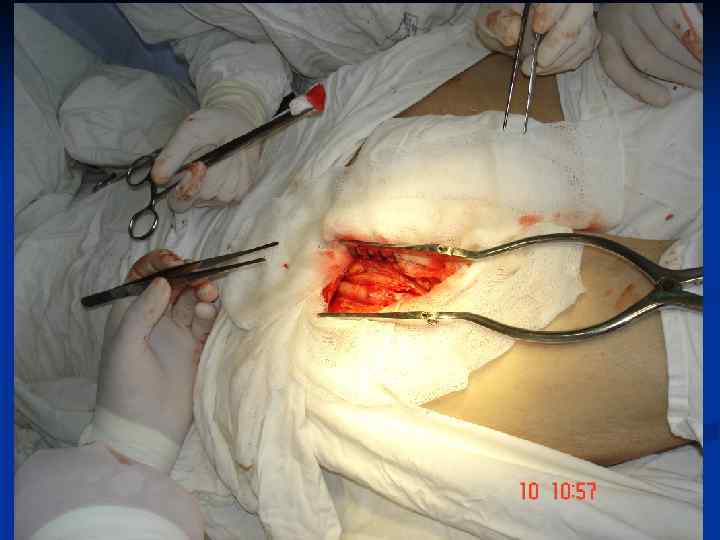

Стегно-підколінне аутовенозне протезування

Стегно-підколінне аутовенозне протезування